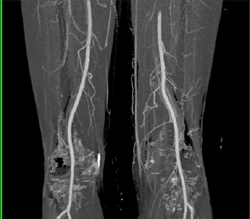

Clot in Superficial Femoral Artery (SFA) Due to Trauma in A Child